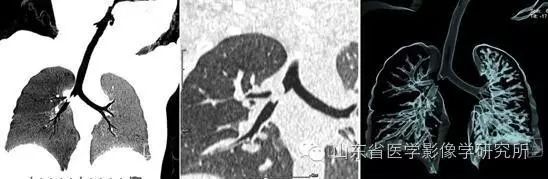

▲ 1岁小孩吃了八宝粥后出现咳嗽、气喘的症状。 低剂量胸部CT扫描+大气道重建后,利用MinIP和VR技术可以清晰显示右主支气管内的异物。

▲ 复杂小儿先天性心脏病的低剂量CTA扫描、先天性心脏病的术前演示和术后评估。